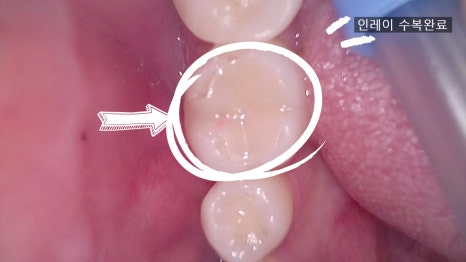

Today, we’d like to talk about an inlay treatment for a man in his 30s.

① Removal of decay and tooth reduction

– The decayed area is removed and the space for the inlay is carefully shaped with precision.

– In the in-house lab, a ceramic inlay is made in the same color and shape as the patient’s tooth.

④ Placement

– After 7 days, the patient returns to have the finished inlay placed, the bite checked, and the treatment completed.